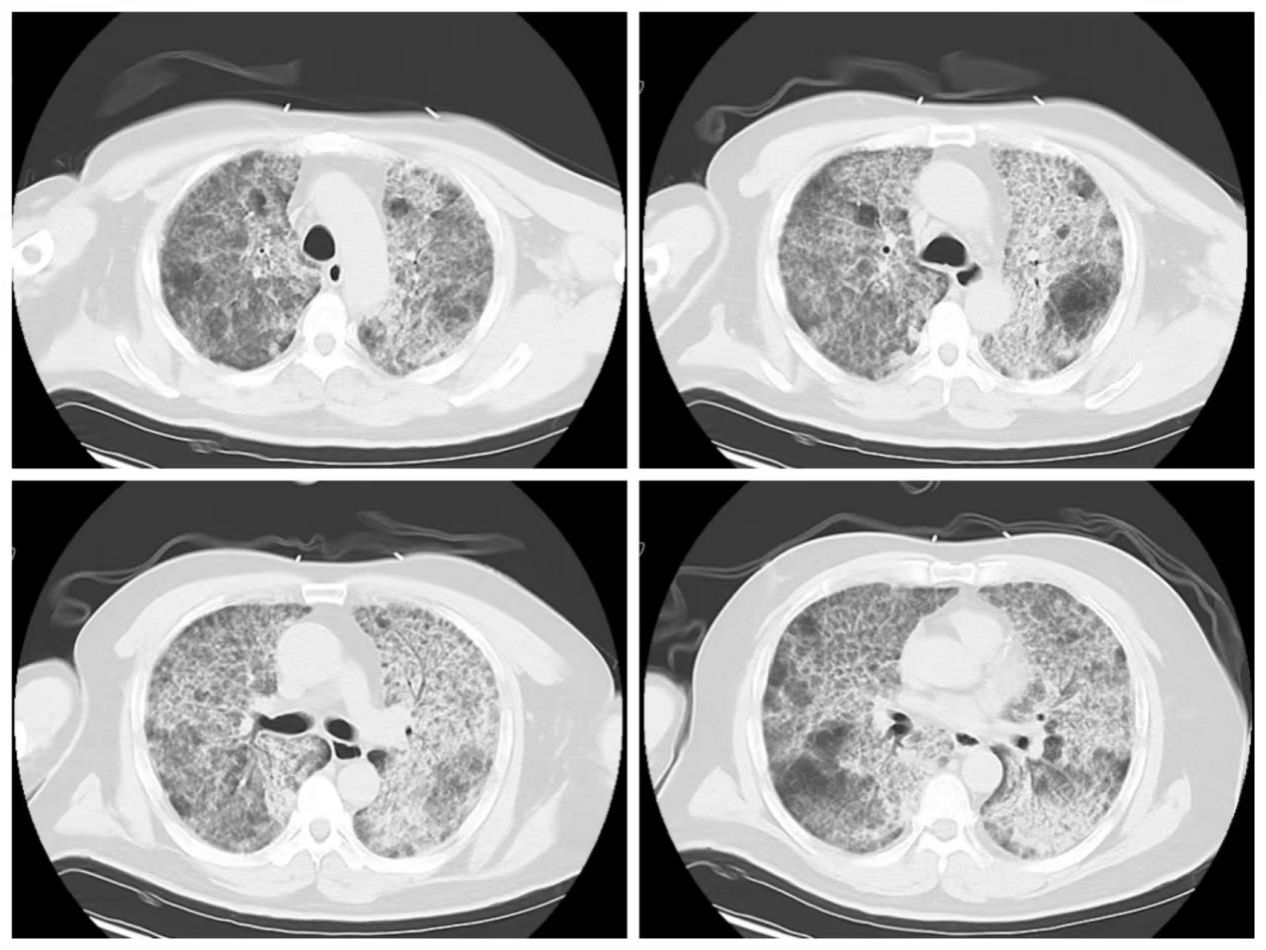

本次救治的患者为50岁男性,早在5年前就因呼吸困难在我院就医,我院呼吸与危重症医学科重症团队凭借丰富的经验很快确诊其为罕见病“肺泡蛋白沉积症”。当时患者已出现呼吸衰竭,动脉血氧分压已低至56mmHg,但患者因个人原因,始终未进行规范治疗及随访,呼吸困难逐年加重。1月前,患者因呼吸困难再次急剧加重,由救护车紧急转入我院。入院时病情极度凶险,鼻导管高流量吸氧指脉氧饱和度仅能维持在70%左右(氧合指数69),生命垂危。收住呼吸与危重症医学科RICU后,方萍主任医师团队立即给予患者无创呼吸机辅助呼吸(吸入氧浓度高达80%),但血氧饱和度仅能勉强维持在88%~90%。胸部CT提示“白肺”,RICU团队成员通过床旁气管镜等检查排除感染,检测患者血清抗粒细胞-巨噬细胞集落刺激因子(GM-CSF)抗体明显升高,进一步明确了“自身免疫性肺泡蛋白沉积症(aPAP)”的诊断。

全肺灌洗前胸部CT